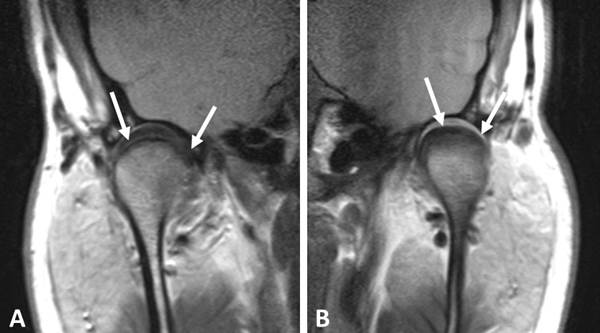

La resonancia magnética proporciona imágenes detalladas de los tejidos blandos, permitiendo evaluar el disco articular, los ligamentos y los músculos asociados a la ATM.

Evaluación mediante resonancia magnética de la ATM